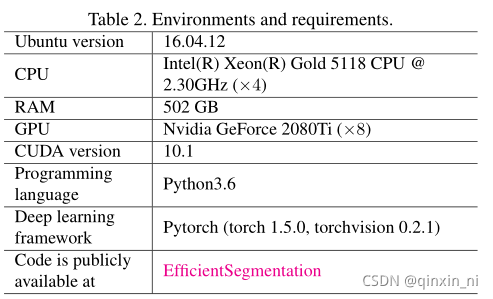

环境配置和需求

Training protocols